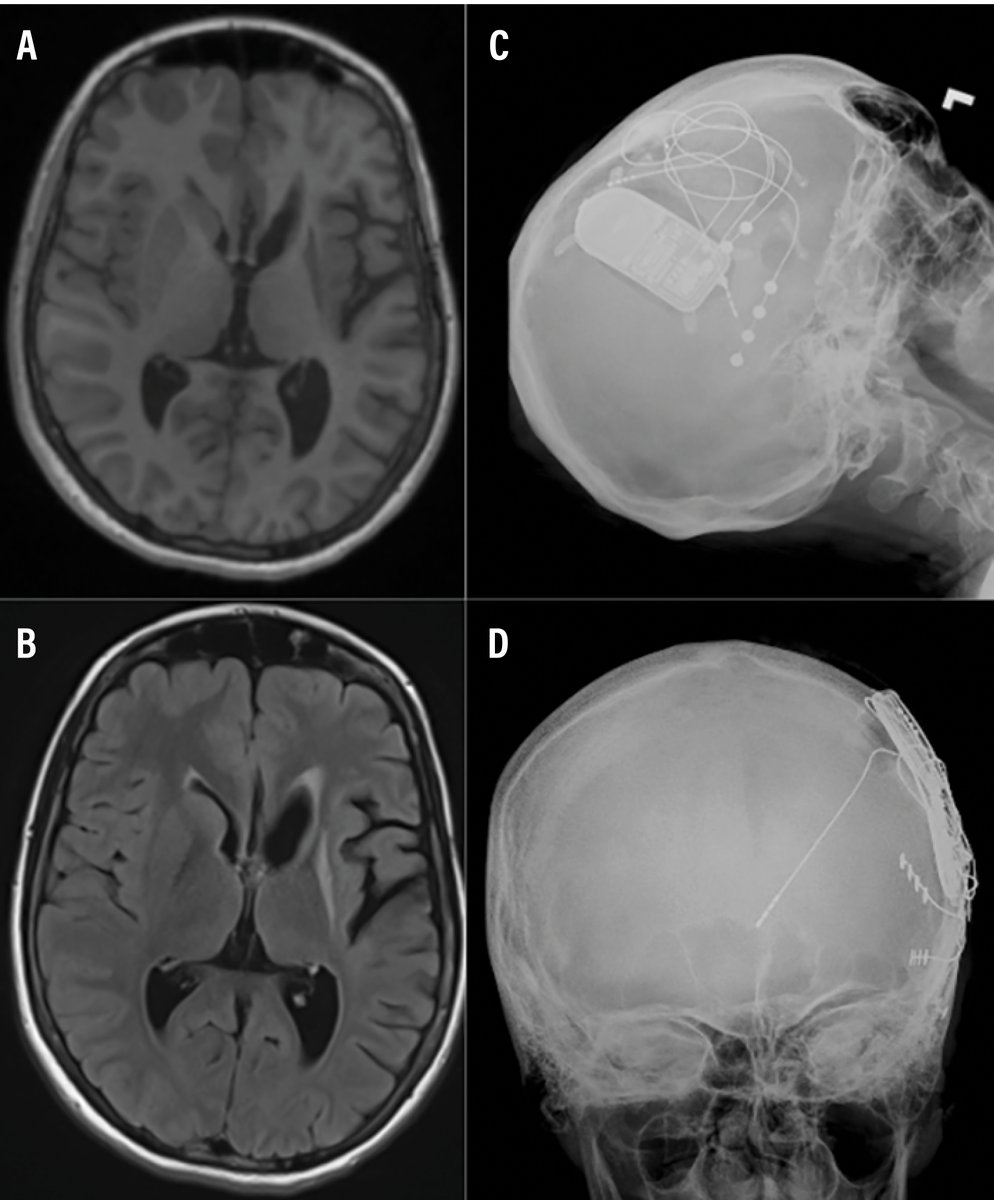

In Lennox-Gastaut syndrome, #neuromodulation approaches—including #VNS, #DBS, and #RNS—offer substantial, durable #seizure reduction when medications fail. Dr Edmonds (@Edmondsbd) discusses these strategies in an article: https://t.co/QHE4pvsnt5

@amepilepsysoc @AANmember

2

4

27